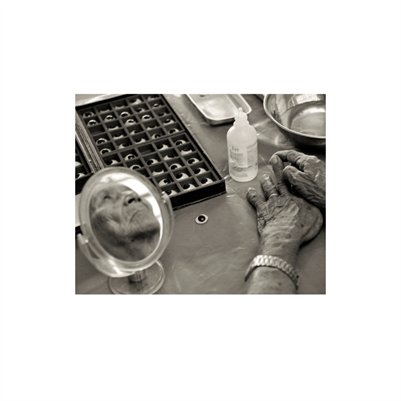

Darkness into the Light. In 2012, The Amazon Project gave eye care to nearly 6000 patients within a 200 kilometer radius of their base in Leticia, Colombia.